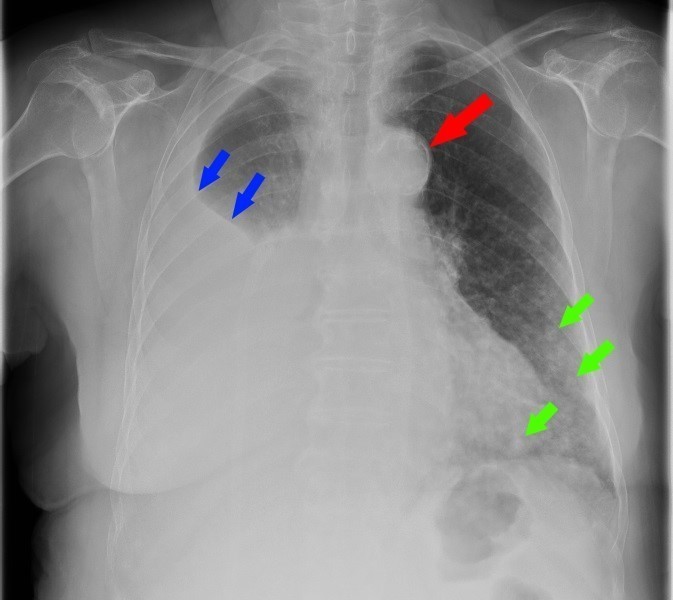

Mme K. est admise aux urgences pour exploration d’une douleur thoracique. Cette femme de 76 ans est suivie en cardiologie depuis dix ans pour un rétrécissement aortique, une hypertension artérielle (HTA) et une dyslipidémie. Elle est parfaitement autonome à domicile. Elle fume un demi-paquet de cigarettes par jour depuis trente ans. Elle est traitée par rivaroxaban (anti-Xa) depuis six semaines pour une thrombose veineuse profonde (TVP) du membre inférieur droit survenue à l’occasion d’un voyage en voiture. Le reste de son traitement comporte de la simvastatine et de l’hydrochlorothiazide.

Depuis trois jours, elle présente une douleur thoracique croissante, latéralisée à droite et survenue sans facteur déclenchant évident.

À évoquer en priorité car TVP récente et douleur thoracique. Le traitement anticoagulant en cours n’élimine pas une migration embolique (surtout en cas de mauvaise observance).

À évoquer devant une douleur thoracique latéralisée.

À évoquer devant une douleur thoracique latéralisée chez une patiente avec tabagisme important.